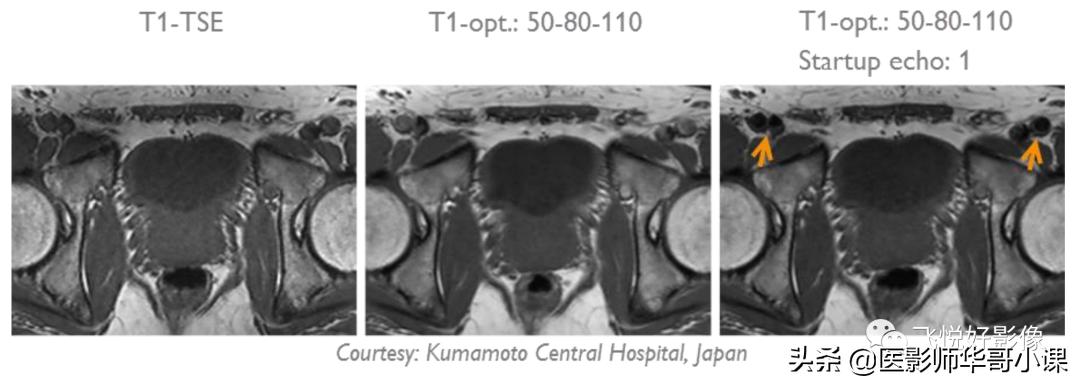

- 对于T2加权图像,使用"T2-optimized"选项:a. 使用小角度聚相脉冲,可以抑制流动伪影;b. 使用较大的"mid. angle"可以减少图像模糊;c. 使用较大的"max. angle"可以提高SNR。

- 对于T1加权图像,使用"T1-optimized"选项:a. 只适用于2D, MS和M2D;b. 如果有截断伪影,可以尝试加一个startup echo;c. "min. angle"和"max. angle"之差太大(~40°)可能导致图像模糊;d. 减小"min. angle"可以提高T1权重,同时可以减少运动伪影;e. 增大"max. angle"可以提高SNR,但是同时也会增大SAR。

- 做任何改动,都要随时 注意 TEeff / TEequiv的变化 。

图7.PSS推荐角度